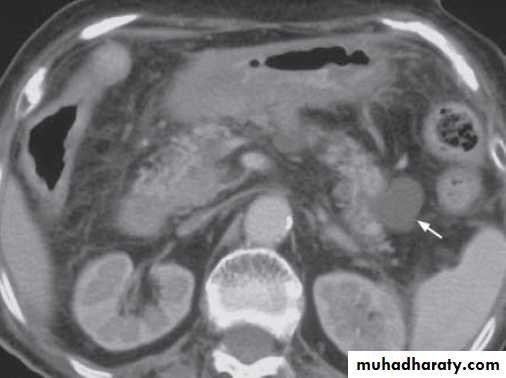

Contrast enhanced axial computed tomography (CT) showing a small pancreatic pseudocyst (arrow) in pancreatic tail in a patient with recent history of pancreatitis.